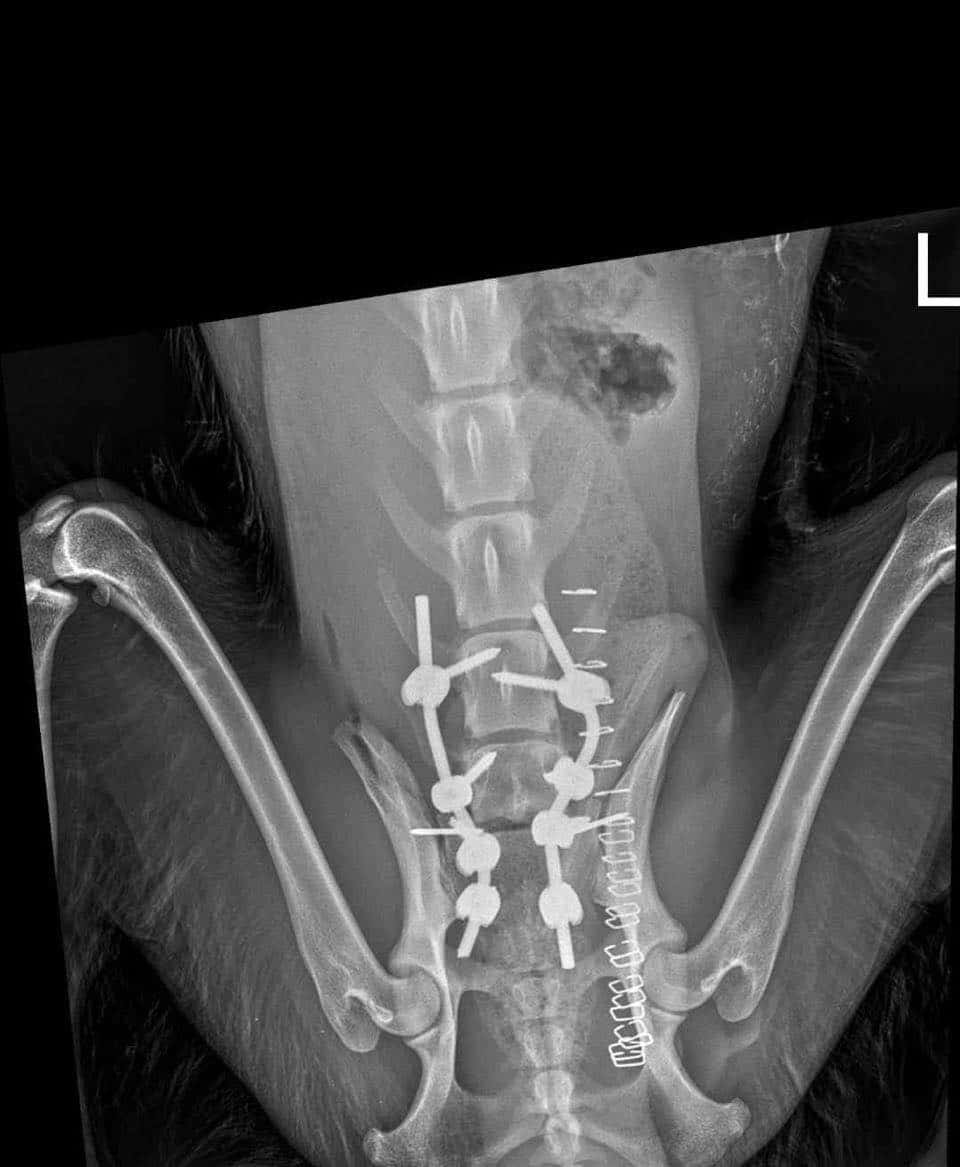

CIPRIAN konnte von unseren Tierschützern vor Ort gerettet werden. Er wurde im Februar 2024 bereits verletzt zwischen die Gleise einer Zugverbindung im Niemandsland gelegt. Aufgrund eines Hinweises konnte er dort geborgen werden und wurde bereits in einer Bukarester Fachklinik an der Wirbelsäule operiert. Inzwischen – Stand Anfang März 2024 – kann er bereits selbstständig wieder laufen, ist aber natürlich noch wackelig und mit kleinen Aussetzern unterwegs.

zur Besonderheit: hatte Wirbelsäulen-OP